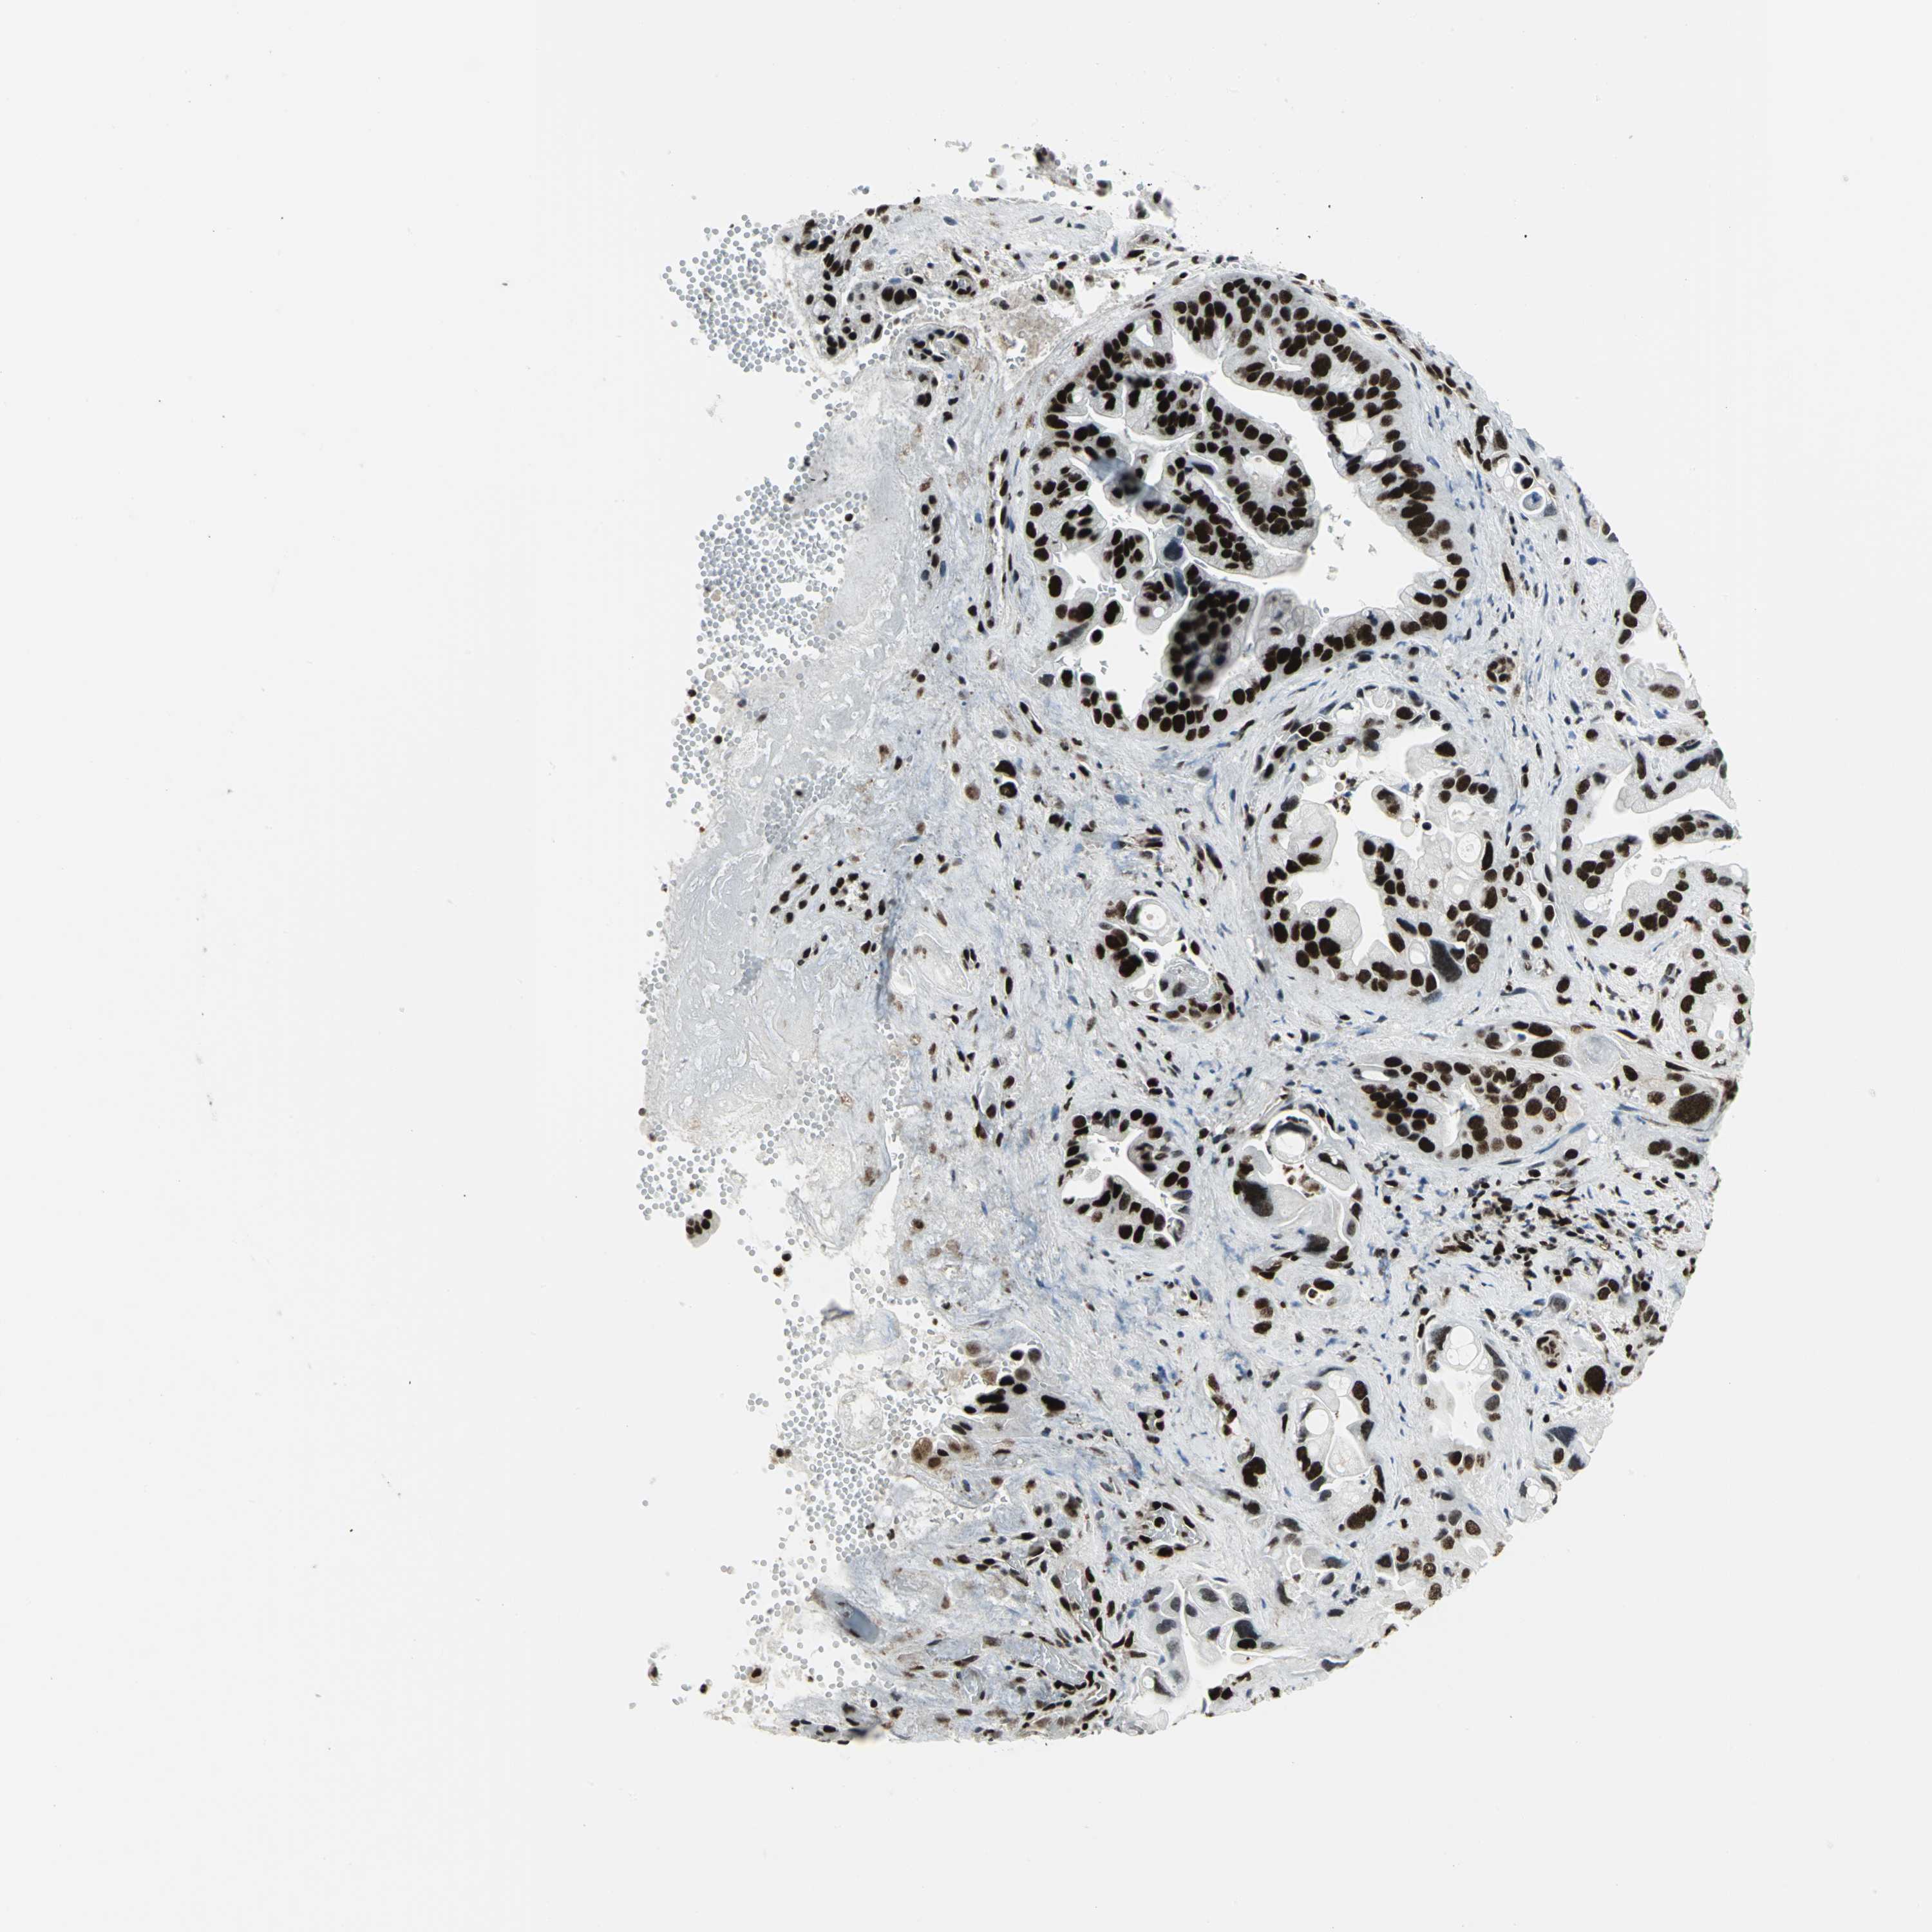

PANCREATIC CANCER - Protein expressioni

A mouse-over function shows sample information and annotation data. Click on an image to view it in a full screen mode. Samples can be filtered based on level of antibody staining by selecting one or several of the following categories: high, medium, low and not detected. The assay and annotation is described here.

Note that samples used for immunohistochemistry by the Human Protein Atlas do not correspond to samples in the TCGA dataset.

Antibody stainingi

Antibody staining in the annotated cell types in the current human tissue is reported as not detected, low, medium, or high, based on conventional immunohistochemistry profiling in selected tissues. This score is based on the combination of the staining intensity and fraction of stained cells.

Each image is clickable and will lead to virtual microscopy that enables deeper exploration of all samples and also displays staining intensity scores, fraction scores and subcellular localization as well as patient and tissue information for each sample.

Antibody CAB004208

Staining

High

Medium

Low

Not detected

Intensity

Strong

Moderate

Weak

Negative

Quantity

>75%

75%-25%

<25%

None

Location

Nuclear

Cytoplasmic/membranous

Cytoplasmic/membranous,nuclear

Adenocarcinoma, NOS

Adenocarcinoma, metastatic, NOS